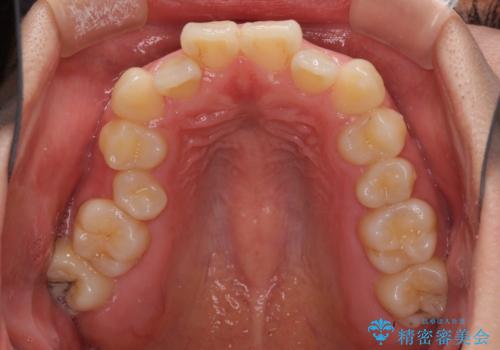

なお、右奥の歯が180度回転した状態で萌出しており、こちらは改善困難なため、そのままの向きで配列することとしました。

右奥の歯が180度回転していることで、噛む度にワイヤーに無理な力がかかったようで、頻繁にワイヤーが切れてしまいました。また、下顎を後方に移動させるためのアンカースクリューも脱離することが多く、治療期間が長くなってしまいました。